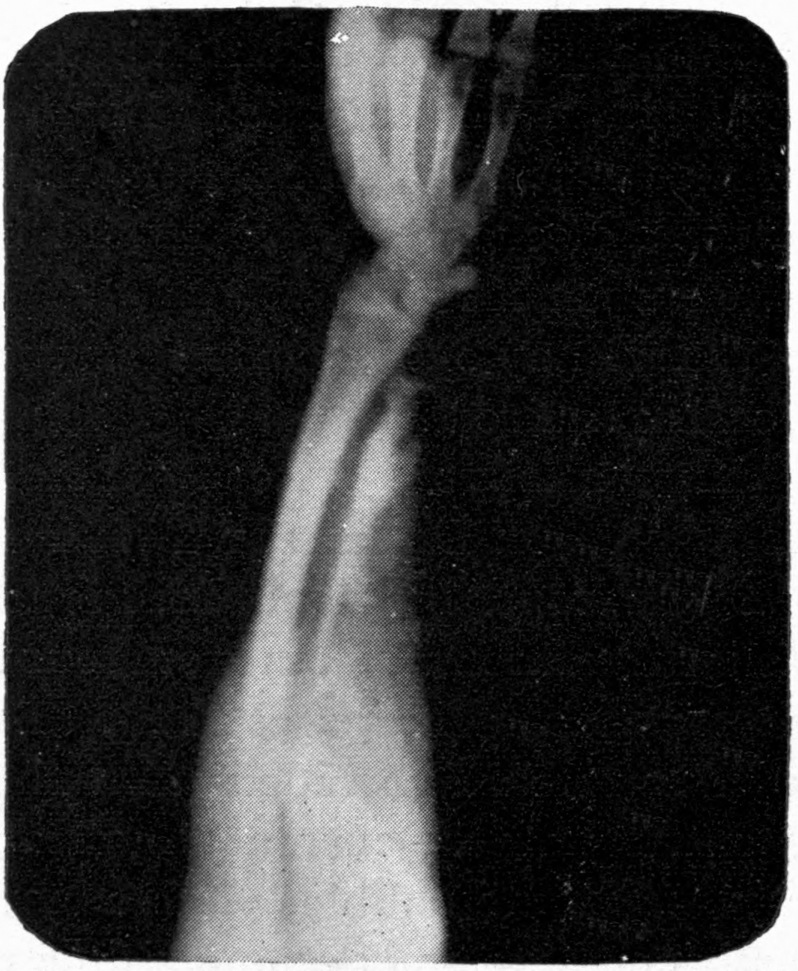

| 156. | Application of X-rays to Distinguish Diamonds and Jet from Imitations. | Buquet, Gascard, and Thompson, S. P. |

Fig. 2.—Broken Arm, Overlapping.

(Due to defective setting.)